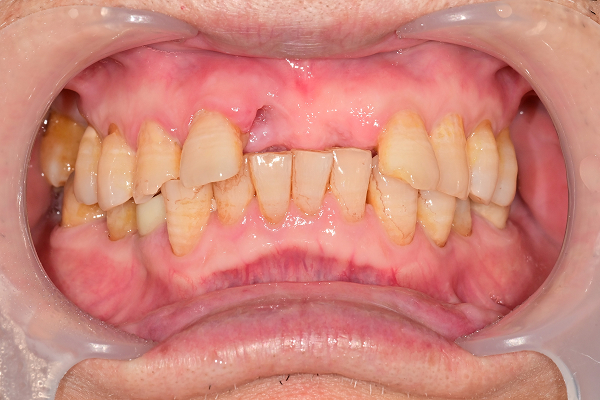

전악 케이스

- 상·하악 전체 보철 설계를 통해 정확한 교합(물림) 회복

- 심미·발음·저작 기능을 종합 고려한 자연스러운 전악 임플란트